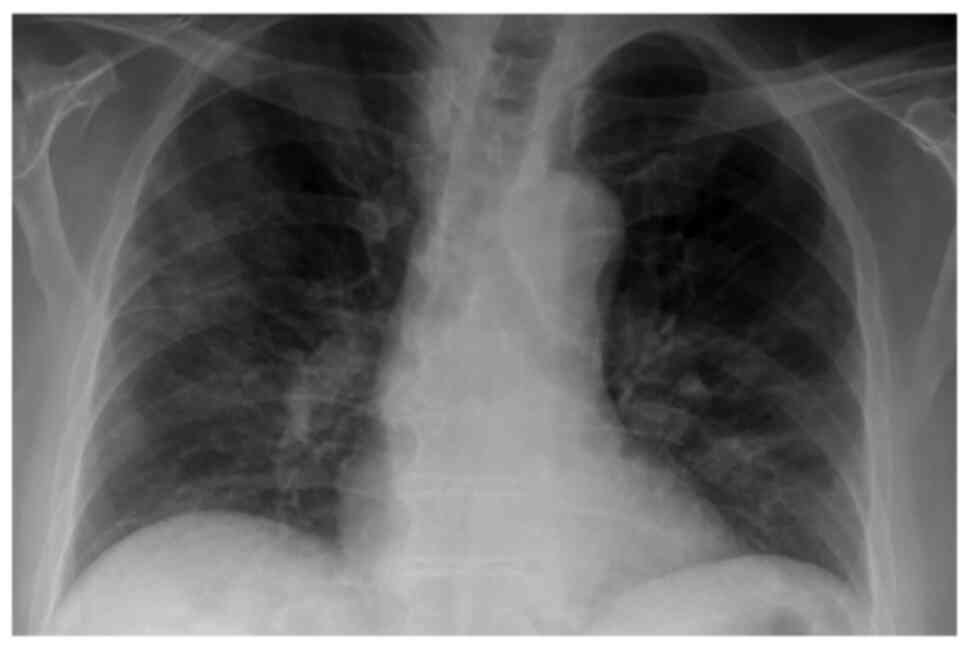

The patient underwent a new chest X-ray, which revealed persistent infiltrates in all lung fields with consolidations in the right upper and middle lung field, and in the left middle lung field (Fig. 5A). He also underwent a chest CT scan and CTPA, which revealed bilateral consolidations with areas of reversed halo sign in all lung fields and peripheral GGO infiltrates in both lower lung lobes (Fig. 5B-D). There were no findings suggesting pulmonary embolism. No infectious microorganisms were isolated from blood and sputum cultures. Based on the clinical and radiological data, COVID-19-associated OP was suspected, and systemic corticosteroid therapy (methylprednisolone at 1 mg/kg/day) was initiated on day 15 (day 28 of illness). On day 18, at 3 days following the commencement of corticosteroid therapy (day 31 of illness), his oxygenation level improved considerably. A chest X-ray and CT imaging performed on day 13 following the commencement of corticosteroid therapy (day 28 of hospitalization, day 41 of illness) revealed a notable improvement in previously noted lung infiltrates (Fig. 6). The levels of CRP also returned to normal. Methylprednisolone administration was decreased to 40 mg, and the patient was discharged on day 33 after admission (day 46 of illness). Following discharge, methylprednisolone administration was decreased to 32 mg for 7 days, 16 mg for 7 days and 8 mg for 7 days, and discontinued thereafter. The patient did not present with a relapse and he had improvement in chest X-ray at a follow-up 2 months after discharge (Fig. 7).

Figure 7

Chest X-ray illustrating a significant improvement in lung infiltrates of the patient in case 2 at the follow-up of 2 months. Please compare this to the image in Fig. 5A.